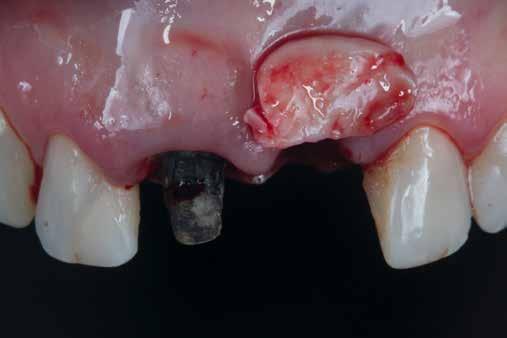

A mindennapi gyakorlatban gyakran találkozunk súlyos fogszuvasodással. A fogorvosnak mindig kihívást jelent a döntés, hogy kihúzzuk és implantátummal pótoljuk, vagy megmentjük a fogat, de kétséges a hosszú távú prognózis. Számos cikkből tudjuk, mint például Seltzer és Kim (Comparison of Long term survival of implant and endodontically treated teeth J Dent Res 93(1):19-26, 2014) cikke, hogy a fogak viszszanyerése jobb megoldás, különösen a fiatalabb betegeknél. A kirakós hiányzó kulcsa az általános fogorvos számára gyakran a maradó fogazat jó biomechanikai értékelése. Az endodontikusan kezelt fogak kudarcainak többsége valójában mechanikai hibákhoz, például repedéshez és töréshez kapcsolódik. A maradó fogszerkezet gondos biomechanikai értékelése, valamint a mechanikai teljesítményt javító technikákra való összpontosítás a legfontosabb a hosszú távú eredmény keresésében. A szerző praxisában a vertikális pre-

parálás és a minimális megközelítés kombinációja, valamint az ortodontikus extrúzió alkalmazása a restauratív fogászatban megváltoztatja a helyzetet, amint azt a következő eset is mutatja.

Egy 35 éves kaukázusi férfi páciens az 1.4-es fog (felső első premoláris) törése miatt kereste fel rendelőnket, a törés ferde volt. A sérült fogak helyreállítása során az egyik legfontosabb lépés a megmaradt fogazat biomechanikai értékelése . Egy hiba ebben a fázisban káros a hosszú távú eredményre . A legtöbb repedést például a fogüregek helyreállító fogászathoz való helytelen előkészítése okozza. Ugyanígy a fennmaradó szerkezet helytelen értékelése idővel mechanikai okokból bekövetkező meghibásodáshoz vezethet.

2. ábra: Az okkluzális nézet a fogszerkezet mennyiségét mutatja, a röntgenfelvételen az 1.5. fogon II. osztályú szuvasodás is látható. Még ha lehetséges is ezeket az eseteket koronahosszabbítással kezelni, a végeredmény átlagosan nem kielégítő. A ferrule gyógyulása korlátozott, és olyan parodontális szövődményekkel is találkozunk, mint a fekete háromszögek, a szomszédos fogak gyökérkitettsége. A fogszabályozó extrúzió sokkal előnyösebb.

4. ábra: A fogszerkezet helyreállítása és a fogrestaurációs komplexum ellenálló képességének javítása érdekében ortodontikus extrúziót végeztek a szomszédos fogakra ragasztott drót és egy egyszerű rugalmas ligatúra segítségével.

5. ábra: Az extrudálás nyomon követése néhány hét múlva. Az extrúzió végén a lágyrészek kisebb mértékű újrakontúrozása történt. A szerző általában fibrectomia nélkül végzi az extrúziót, és az extrúzió végén a lágyrészek újrakontúrozását végzi.

6. ábra: A fog az extrúzió és a függőleges preparálás után. A függőleges preparáció a legjobb preparátum a fog szerkezetének megőrzése szempontjából, különösen akkor, ha minimálisan invazív megközelítéssel alkalmazzák. A szerző egy módosított vertikális technikát alkalmaz, amely nagyobb hangsúlyt fektet a pericervikális dentin fenntartására.

7. ábra: A bukkális szerkezet összehasonlítása extrudálás előtt/után . A maradék fogazati struktúra okklusális terhelése most sokkal kedvezőbb a hosszú távú eredmény szempontjából .

8. ábra: Ideiglenes eltávolítás. 9. ábra: Még a szájpadlásfalon is volt fogazati struktúra-gyarapodás. A szájpadlásfal mintegy 35%-a már szilárd fogazati struktúrán van. Ez a jobb biomechanika miatt sokkal jobb eredményt tesz lehetővé a későbbi restauráció számára.

10. ábra: A cirkónium-dioxid korona cementálása üveg-ionomer cementtel . Ezzel a megközelítéssel nyilvánvaló, hogy a ferrule menynyisége a szomszédos fogakra gyakorolt bármilyen komplikáció nélkül nyert. A parodontális apparátus valójában érintetlen. Nincsenek fekete háromszögek, nincs a szomszédos fogak gyökérkitettségének kockázata. Már a szülés napján megvan a papilla, amely kitölti az intraproximális tereket. A nyert ferrule mennyisége hatalmas. A bukkális falon könnyen felismerhetjük, hogy az egész fal már szilárd fogazati struktúrán van, a palatális falon pedig az ajánlott 1-1,5 mm-nél jóval több. A függőleges preparálással szintén könnyen meg tudjuk tartani a visszanyert fogszerkezet mennyiségét , különösen a pericervikális dentin területén, ami a legfontosabb a hosszú távú eredmény szempontjából.